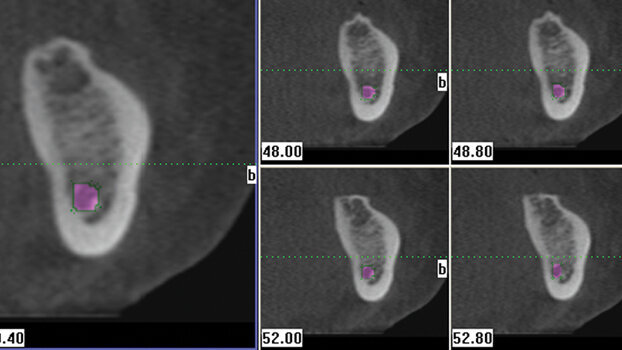

Following what seemed to be a root canal failure in tooth No. 14 based on clinical and radiographic diagnosis with a conventional two-dimensional periapical...